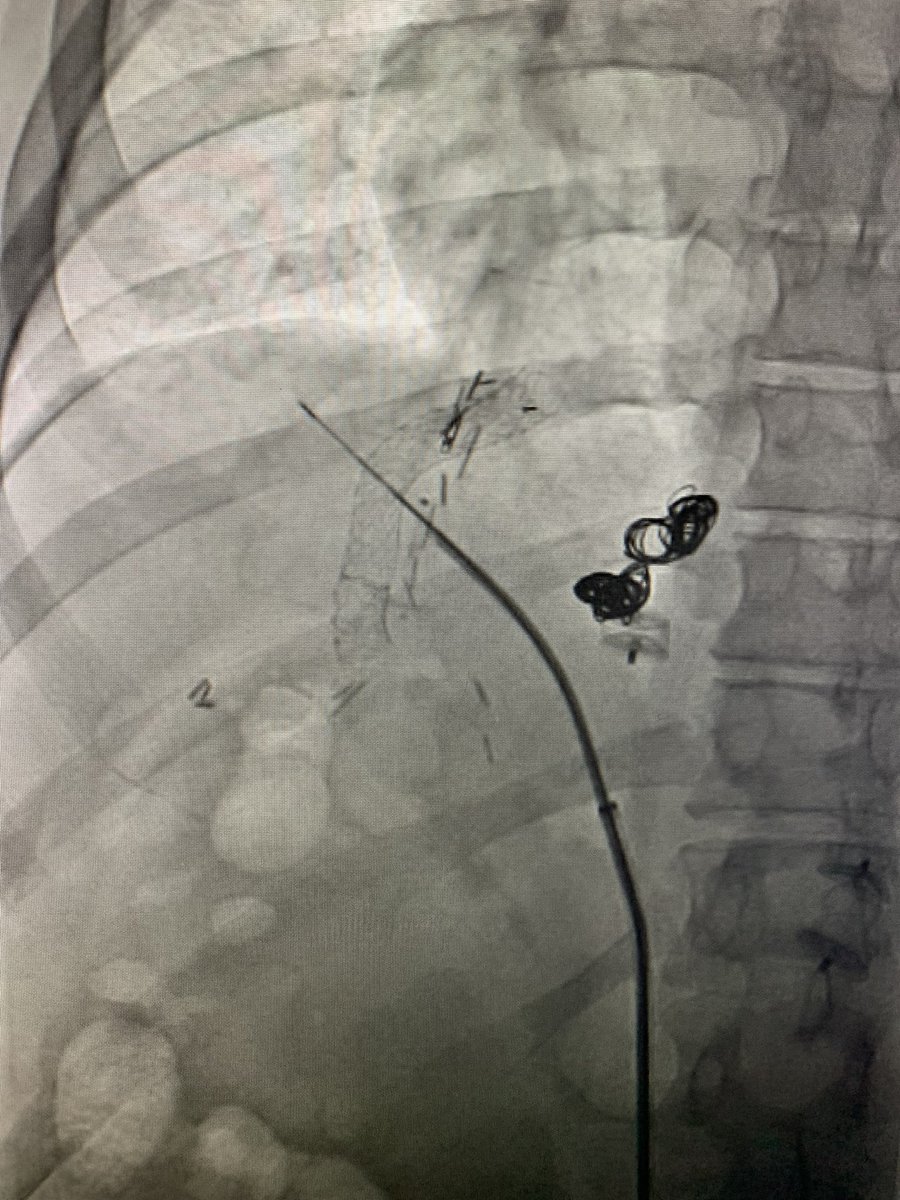

Massive hemoptysis in setting of PNA and anticoagulation. POSITIVE bleed seen from selective bronchial art run 🫁🩸👀. No more hemoptysis after bronchial art embo (BAE) w 300-500 micron particles. The Dotter Institute Ryan Schenning, MD SIR ECS SIR RFS

Massive hemoptysis in setting of PNA and anticoagulation. POSITIVE bleed seen from selective bronchial art run 🫁🩸👀. No more hemoptysis after bronchial art embo (BAE) w 300-500 micron particles. <a href="/dotter_IR/">The Dotter Institute</a> <a href="/Ryan_Schenning/">Ryan Schenning, MD</a> <a href="/SIR_ECS/">SIR ECS</a> <a href="/SIRRFS/">SIR RFS</a>